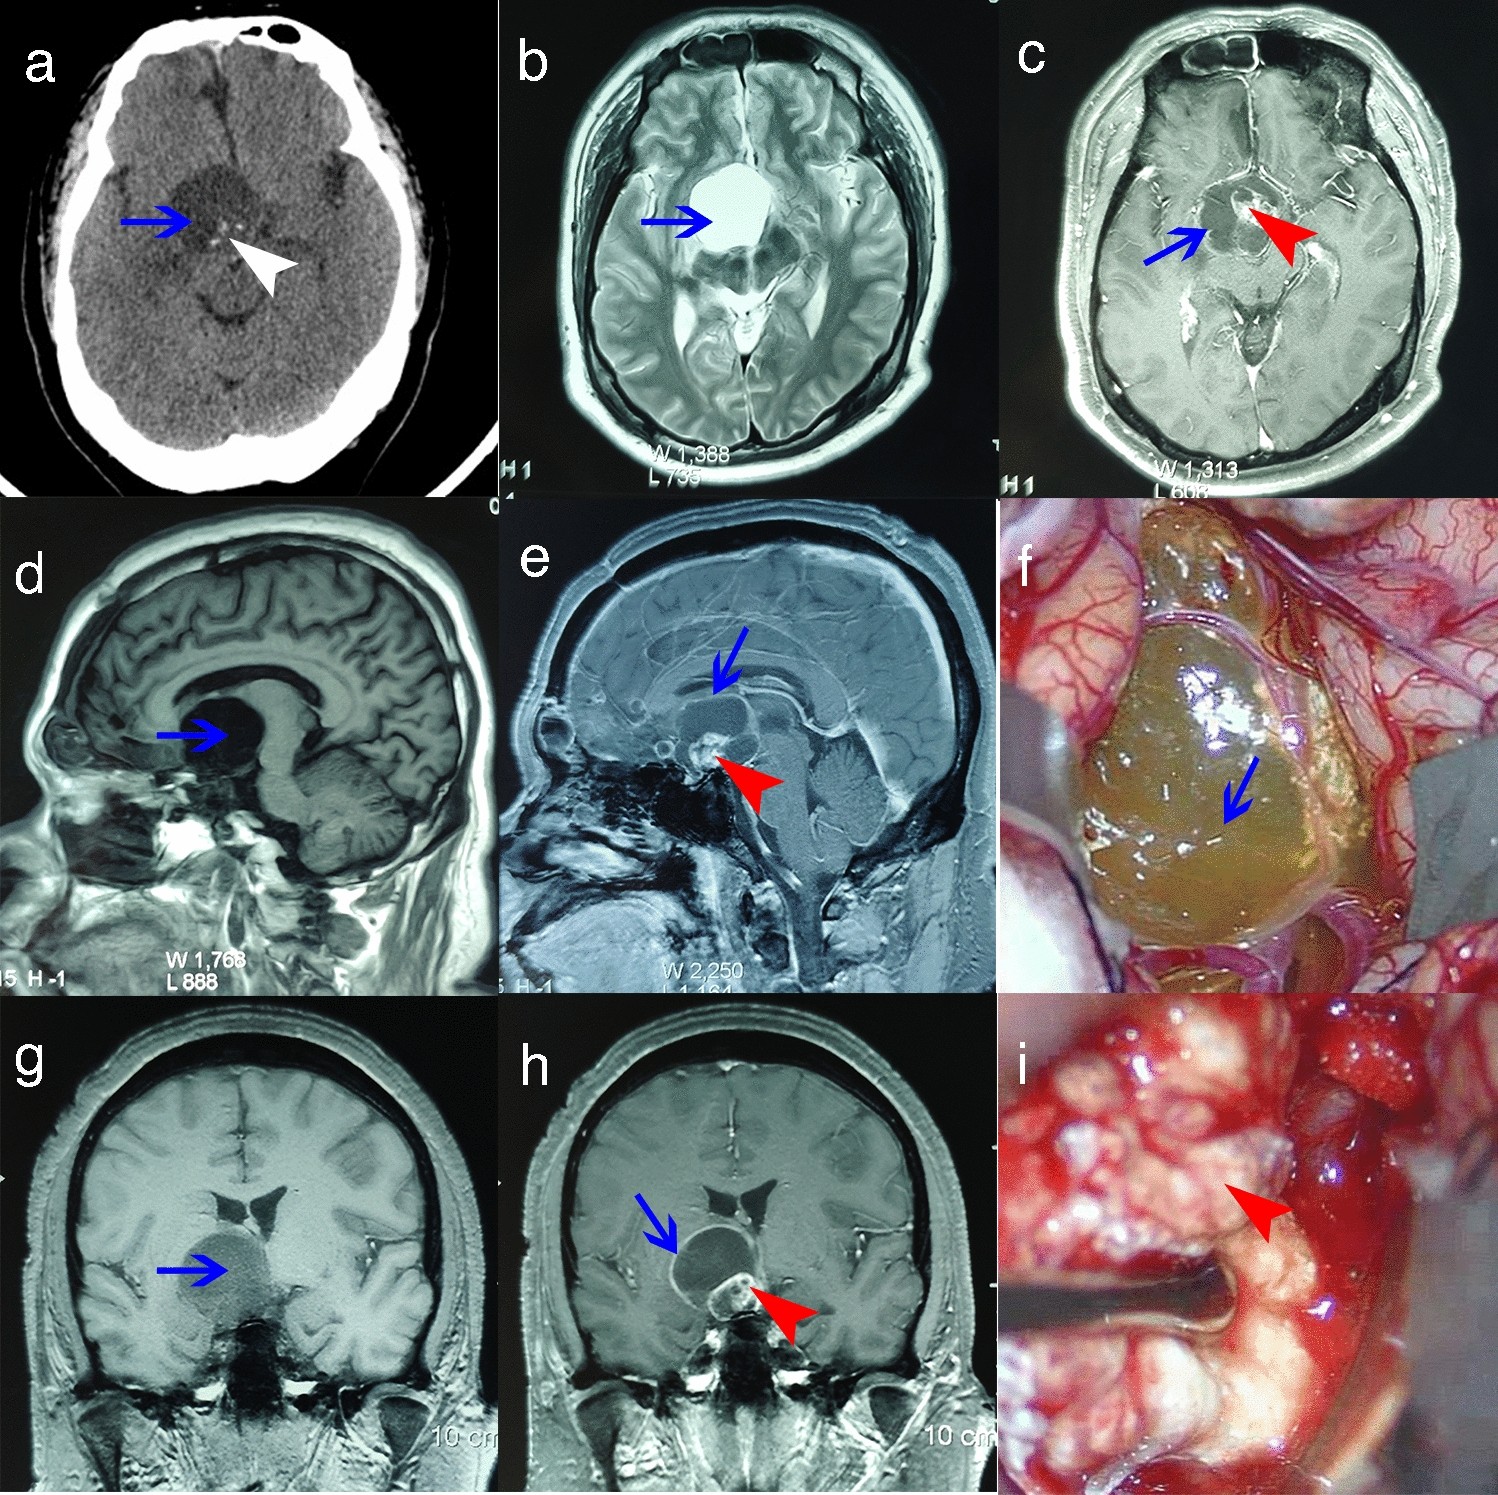

Preoperative and intraoperative imaging of cyst wall and solid body. (a) CT scan shows low-density cystic lesion and high-density calcifications (blue arrow, cyst; white arrowhead, calcifications). (b) T2-weighted axial MRI shows hyperintense signal lesion (blue arrow: cyst). (c,e,h) T1-weighted enhanced MRI shows the peripheral cyst wall and heterogeneous solid body (blue arrow, cyst wall; red arrowhead, solid body). (d,g) T1-weighted MRI shows hypointense signal lesions (blue arrow: cyst). (f,i) Cyst wall and solid body during operation (blue arrow, cyst wall; red arrowhead, solid part).